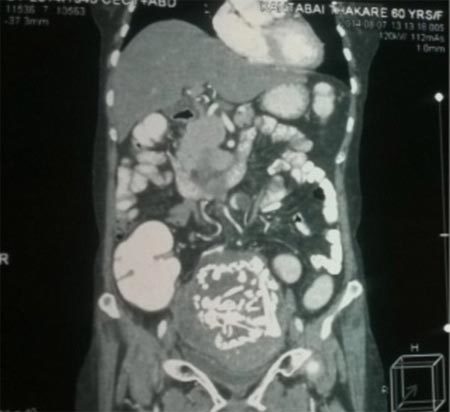

Kết quả chụp cắt lớp vùng bụng của bà Thakrehé lộ khối u chứa một bộ xương phát triển đầy đủ, được bao bọc trong một túimàng đã canxi hóa. Ảnh: Cover Asia Press |

Khi khám lâm sàng, các bác sĩ phát hiện một khối u ở phía dưới, bên phải bụng của bà Thakre. Ban đầu họ e ngại đây có thể là ung thư, nhưng kết quả siêu âm và chụp cắt lớp hé lộ, một khối vật chất cứng, đã bị canxi hóa trong cơ thể bệnh nhân lớn tuổi.

Nhóm bác sĩ tiến hành phẫu thuật cho bà Thakre sau đó phát hiện, khối u chứa một bộ xương phát triển đầy đủ, được bao bọc trong một túi màng đã canxi hóa. Khối u nằm giữa tử cung, ruột và bàng quang cũng như bám chắc vào tất cả những cơ quan nội tạng này.